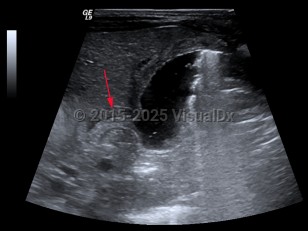

EchinococcosisEchinococcosis